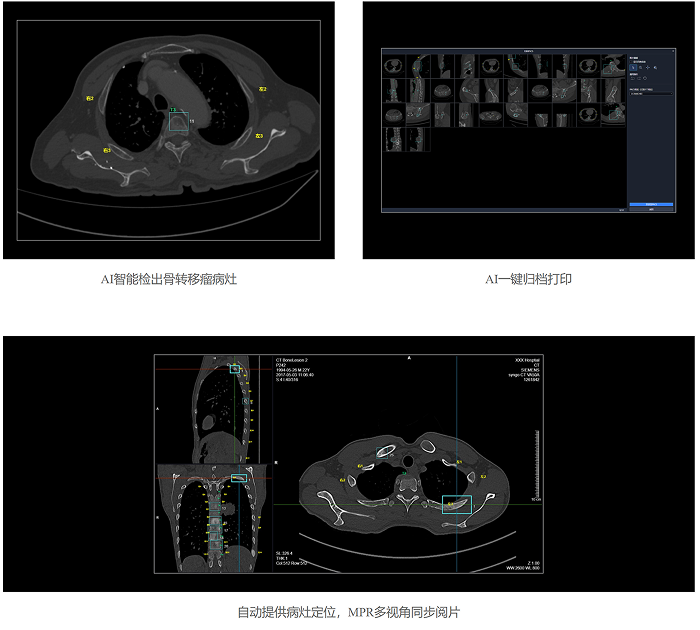

联影智能CT骨转移智能分析系统可秒级检出及分类原发骨肿瘤、溶骨性骨转移、成骨性骨转移、混合型骨转移与其他骨异常病灶,同时精准标识肋骨、椎体、盆骨位置,自动提供病灶定位信息,系统支持MPR三视图同步对比阅片、一键归档PACS功能,辅助医生高效、精准地完成肋骨、椎骨与盆骨骨疾病的诊断,避免漏诊。

联影智能CT骨转移智能分析系统支持多部位、多病灶类型的智能检出,自动标记骨头及定位病灶,极大降低了漏诊概率。其智能随访功能能自动精准配准图像,协助医生高效评估病情发展。系统还支持手动新增和编辑病灶,以及自动生成检查所见,有效提升了医生的工作效率和诊断准确性,为骨转移瘤的精准诊疗提供了强有力的支持。